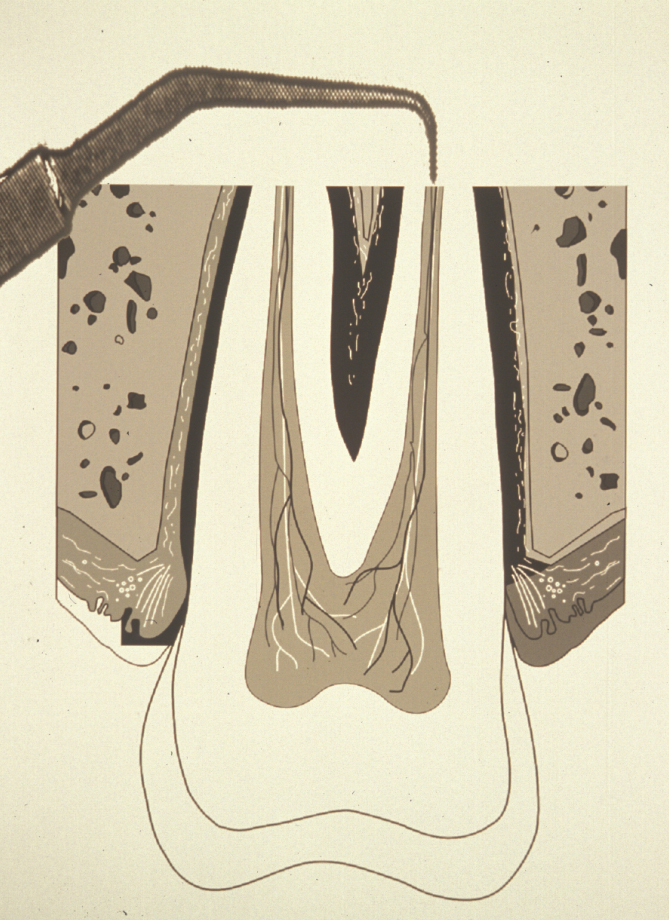

The aim of root end resection is to present the surface of the root so that the apical seal of the orthograde root filling can be examined, and to provide access for root end preparation. Approximately 2 to 3 mm of the root end is resected at right angles to the long axis of the tooth. A bevelled resection is avoided where possible because a larger surface area of dentinal tubules is exposed, which can lead to microleakage. Also, if the root end is bevelled, there is the possibility of leaving behind infected tooth tissue, or of missing part or all of the root canal system (Figure 3).

Root end resection is effectively an apicectomy, and although the term ‘apicectomy’ has been commonly used to describe apical surgery, it only describes a small section of the whole procedure and is, therefore best avoided.